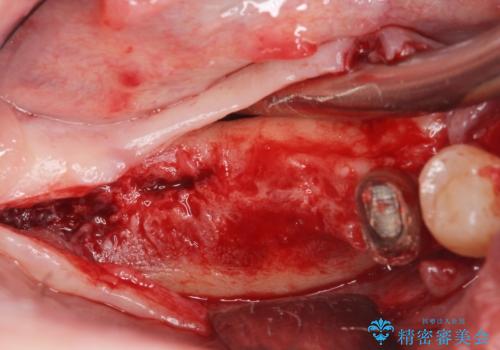

- 歯周病が進行し、根尖付近まで歯槽骨(歯を支える骨)の吸収が見られる歯の治療を希望され来院されました。

長期的な予後の見込めない奥歯の抜去を行い、骨と歯ぐきの治癒を待ち、インプラント治療を計画します。

インプラント周囲には骨の増生を埋入時に同時に行っています。